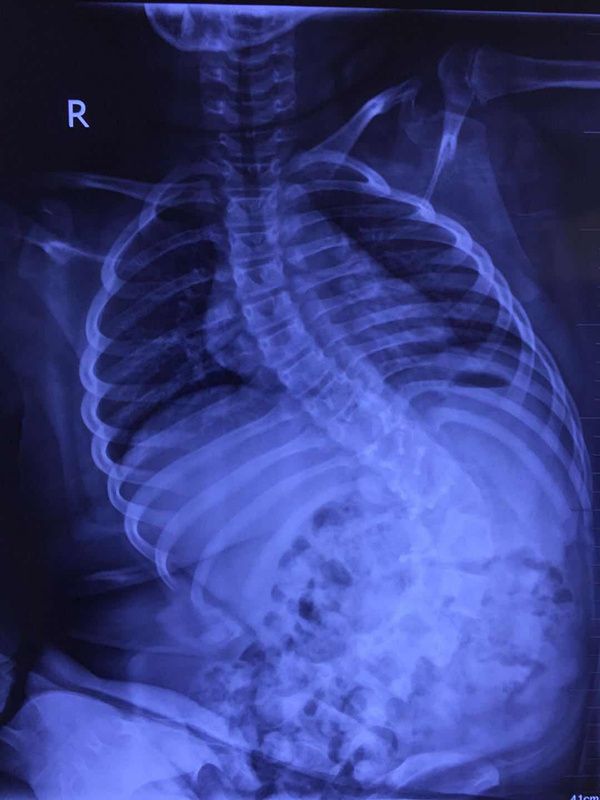

20世纪60年代医学专家在新生儿尸检中发现:儿童脊柱能够延长至5—6厘米,而脊髓只能够牵拉0.6厘米,这说明儿童脊柱延展性很强,而脊髓延展性差。同时,反复下腰时,可能导致脊髓的小血管损伤或栓塞等,引起脊髓缺血性损伤、静脉高压。因此,发病儿童在下腰时直接就是脊髓损伤,而没有明显的脊柱骨折和脱位。这是儿童脊髓损伤的显著特征。

郭晓东的研究团队发现,受伤儿童在下腰运动过程中,脊柱纵向牵拉损伤脊髓,神经轴突、神经细胞和小血管的钝性损伤,医学上叫“急性过伸性脊髓损伤”,直接主要原因就是舞蹈练习中的下腰。

在临床上,儿童下腰导致的脊髓损伤,有的会诊断为无骨折脱位型脊髓损伤、脊髓损伤或者误诊为脊髓炎。为了引起社会公众警惕,郭晓东教授研究团队在完成研究后,给这种灾难性疾病取了一个通俗的名字——下腰瘫,并写入论文中。

郭晓东研究团队找到了2010年9月至2020年9月在武汉协和医院诊断及治疗的共44例儿童下腰瘫患者的资料。44个孩子,女孩有42例,占95.5%,男孩2例,占4.5%。44个小患者年龄在3岁到10岁之间,8岁及8岁以下的有41例,占比95.3%。他们患病前参加舞蹈训练的时间在2个月到2年之间。

从颈部到骶尾的脊柱是人体最大的支撑,脊柱的椎管包裹并保护着的脊髓是人体中枢神经之一(另一个中枢神经是大脑)。由于具体的发病机制不清楚,和其他类型的脊髓损伤一样,儿童下腰瘫的治疗和康复也是一个世界难题。

回顾性研究发现,纳入研究的44名儿童,发病后有29例腰痛,16例下肢疼痛,13例下肢麻木或者乏力。这44个孩子出现症状后有27例继续下腰或者做其他训练项目及活动,有12例在一旁休息(但是仍在随意活动),有4例即刻出现下肢不能站立、活动并哭闹,才被迫停止活动。